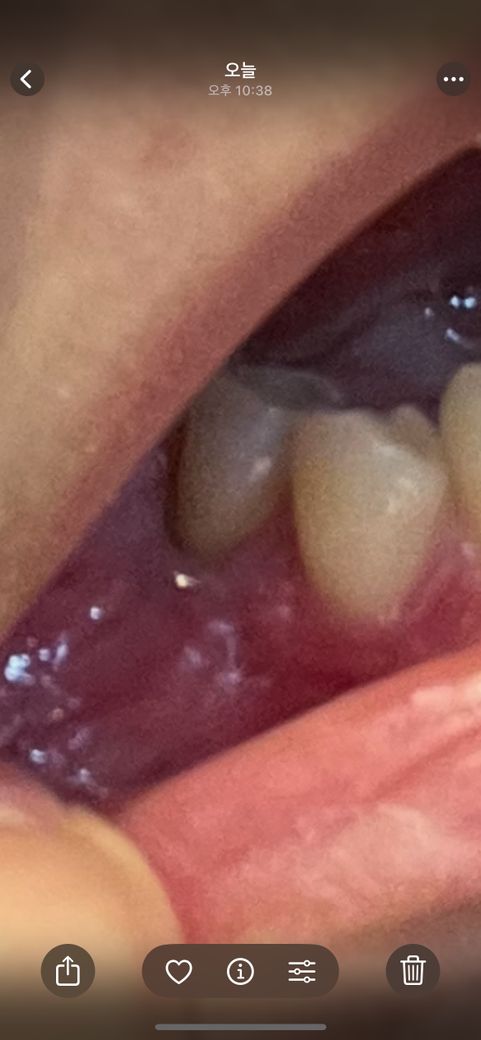

치근단절제술 후 재발?? ㅜㅜ사진 봐주세요..

안녕하세요 제가 5월 중순쯤 치근단 절제술을 했어요

1번 전신마취로 하고 두세번 소파술(?)로 긁어내고 얼마전에 한번 더 했어요 교수님이 치아 보존해주시려고 엄청 노력해주신것 같아요 ㅠㅠ

저번주 금요일 찍은 사진이랑 오늘 찍은 사진입니다. 색이 좀 하얗게 변한것 같은데

이거 괜찮은것 맞나요? 낫는 과정인지 염증재발 한건지 궁금합니다..

• 1번 째 사진

• 2번 째 사진

사진으로 봤을 경우에는 해당 부위에 붓기가 있는 것으로 보입니다. 잇몸에 붓기가 있는 원인은 내부에 감염 등이 되었을 경우입니다. 이런 경우에는 붓기를 제거해 주거나 염증 원인을 제거해 주는 것이 좋습니다.

저 사진 보고 염증이 개선됐다 안됐다 판단은 어려워요 전, 후 엑스레이 사진이 있어야 합니다